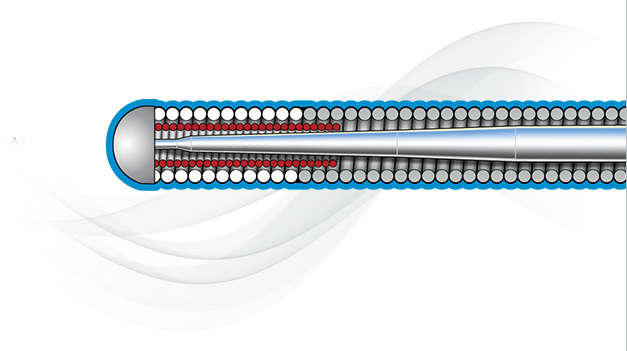

Inner Coil Technology

The advanced design of the stainless steel core and Inner Coil Technology provides a unique combination of exceptional torqueability, rail support, and shape retention.

- Stainless steel inner coil affixed directly to the distal end of the guidewire core

- Improved durability and ease of shaping

- Exceptional torqueability without whipping

Micro EMTTM Technology

MICRO EMT exactly matches the taper of the core and coil, allowing for a lower profile and a more flexible core, leaving almost no room for the core to move within the coil, resulting in 1:1 torque.

- Entry: The smallest tip on the market (0.008”) and the long taper (6 cm) facilitate easy lesion entry in even the most complex lesions.

- Maneuverability: A flexible distal shaft enables excellent intraluminal navigation in complex lesions, with minimal perforation risk.

- Torque: With exactly matched tapers, the core and coil move as one, eliminating whip and empowering precise steerability.